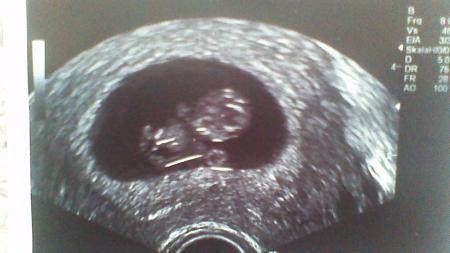

Mamschi2015

So sieht meine Erbse aus :-)

Bild zu